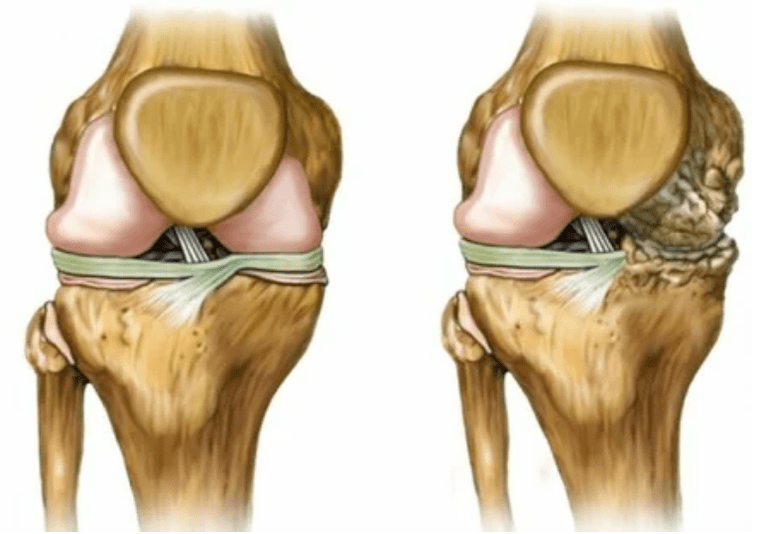

- Deformazione articolare, la cartilagine acquisisce una forma irregolare, provocando curvatura;

- 3 gradi. Spesso ci sono dolori, è difficile spostare l'arto a causa dei cambiamenti nell'articolazione. Le lesioni sono estese, diventano evidenti all'aspetto nudo. Si verifica la deformazione del sito articolare, l'area interessata si gonfia e diventa rossa. L'asse dell'arto è disturbato, il che porta alla complessità del movimento. I cambiamenti patologici provocano l'accorciamento dei legamenti. Compaiono subbluishi e contratture. I muscoli adiacenti sono abbreviati o allungati, da cui la funzione contrattile è indebolita.

Deformazioni degli arti. Appare in una forma trascurata della malattia, indica la completa distruzione del tessuto della cartilagine e la comparsa degli osteofiti. In questo stato, la pressione sulle articolazioni sulla parte superiore e inferiore aumenta, da cui la curvatura può influire sull'intero arto.